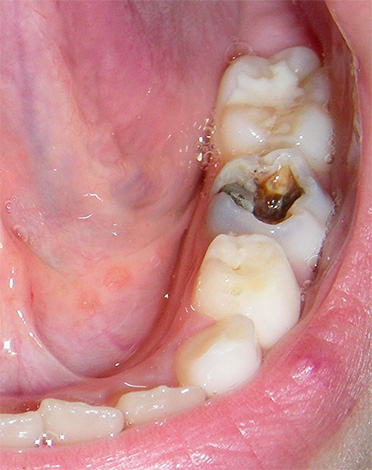

La foto seguente mostra carie delle fessure, cioè localizzato nell'area del sollievo naturale dei denti. Sotto tale oscuramento, i tessuti significativamente distrutti sono spesso nascosti all'interno, che non vengono immediatamente rilevati durante un esame di routine:

A casa, una tale "carie interna" è quasi impossibile da rilevare. Si rilascia solo con un esteso danno alla dentina e la comparsa di dolore al dente quando la polpa è inclusa nel processo patologico. Ecco perché le visite profilattiche dal dentista sono così importanti che metodi speciali possono rilevare la carie in qualsiasi sua localizzazione e curare il dente prima che sia necessario rimuoverlo (rimozione del nervo).